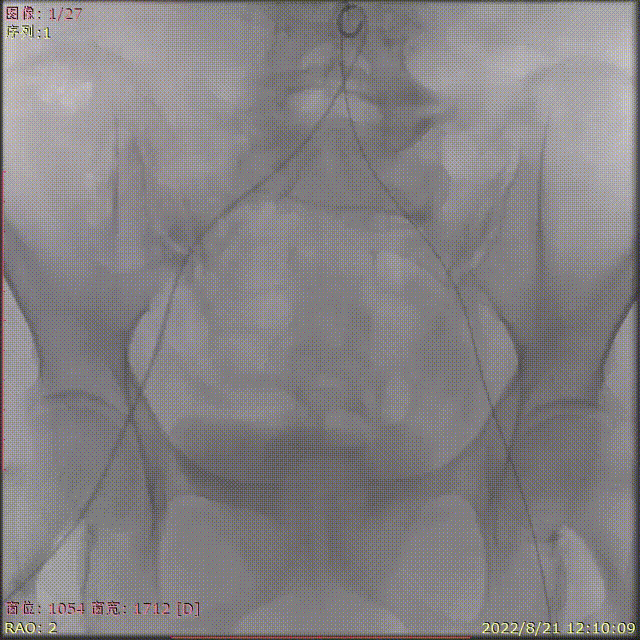

术中剪影

手术影像记录

主动脉根部造影

18mm球囊预扩

输送器顺利过弓跨瓣

瓣膜初始定位

工作位多角度评估瓣膜形态,位置理想

缓慢稳定完全释放瓣膜

球囊后扩,改善瓣膜形态

最终造影,位置理想,无瓣周漏

外周造影检查